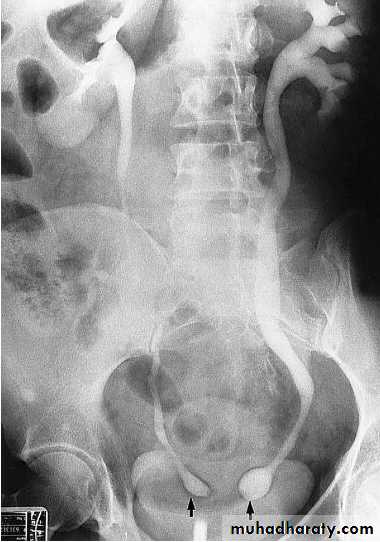

Bilateral ureteroceles. dilatation of the distal ureter as it enters through the bladder wall. This produces a typical “cobra head” deformity (arrows.